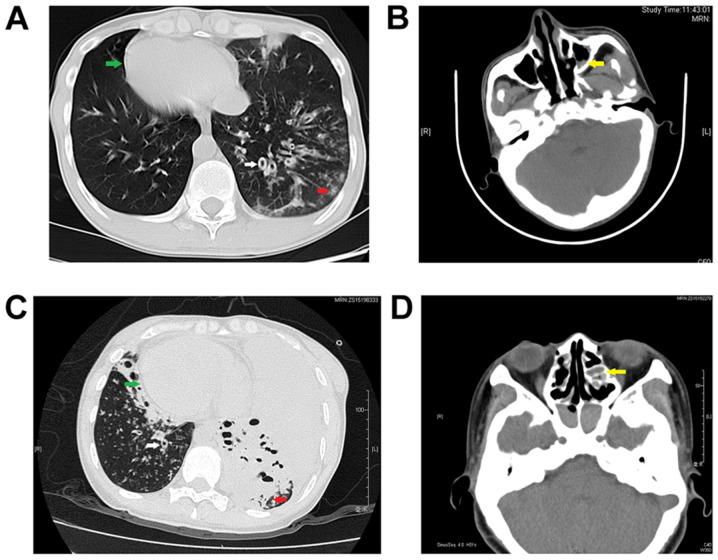

Primary ciliary dyskinesia (PCD) is a rare, genetically heterogeneous disorder caused by dysfunction of the cilia and flagella; however, causative genetic defects have not been detected in all patients with PCD. Seven Chinese Han patients with Kartagener syndrome were enrolled onto the present study. Transmission electron microscopy (TEM) was performed to evaluate the cilial defects and whole‑exome sequencing was used to analyze relevant genetic variations in all patients. In two of the seven patients with PCD, four novel dynein axonemal assembly factor 1 (DNAAF1) mutations were identified (NM_178452.6:c.3G>A, c.124+1G>C, c.509delG and c.943A>T) in three alleles. Both of these patients had long‑standing infertility. Their chest computed tomography results showed bronchiectasis, lung infections and situs inversus, and paranasal computed tomography revealed sinusitis. Semen analysis of the male patient showed poor sperm motility. TEM showed defects in the inner and outer dynein arms in both patients. The DNAAF1 sequences of family members were then analyzed. Bioinformatics analysis indicated that these mutations may be the cause of the cilial defects in these two probands. Thus, the present study identified novel PCD‑causing mutations in DNAAF1 in two patients with PCD. These genetic variations were predicted to alter DNAAF1 amino acid residues and lead to loss of function, thereby inhibiting cilia‑mediated motility. Accordingly, the two probands had PCD symptoms, and one of them died due to PCD‑associated complications.

原发性纤毛运动障碍(PCD)是一种罕见的、遗传异质性疾病,由纤毛和鞭毛功能障碍引起;然而,并非所有 PCD 患者都能检测到致病的遗传缺陷。本研究纳入了 7 名患有卡塔格内综合征的汉族中国患者。通过透射电子显微镜(TEM)评估纤毛缺陷,并对所有患者进行全外显子组测序以分析相关的遗传变异。在 7 名 PCD 患者中的 2 名患者中,在 3 个等位基因中发现了 4 种新型动力蛋白轴突组装因子 1(DNAAF1)突变(NM_178452.6:c.3G>A、c.124+1G>C、c.509delG 和 c.943A>T)。这两名患者均有长期不孕史。他们的胸部计算机断层扫描结果显示支气管扩张、肺部感染和内脏转位,以及副鼻窦计算机断层扫描显示鼻窦炎。男性患者的精液分析显示精子活动力差。TEM 显示这两名患者的内外动力蛋白臂均存在缺陷。然后分析了家庭成员的 DNAAF1 序列。生物信息学分析表明,这些突变可能是这两个先证者纤毛缺陷的原因。因此,本研究在 2 名 PCD 患者中鉴定了 DNAAF1 引起的新型 PCD 致病突变。这些遗传变异预计会改变 DNAAF1 的氨基酸残基并导致功能丧失,从而抑制纤毛介导的运动。因此,这两个先证者都有 PCD 症状,其中一个因 PCD 相关并发症而死亡。